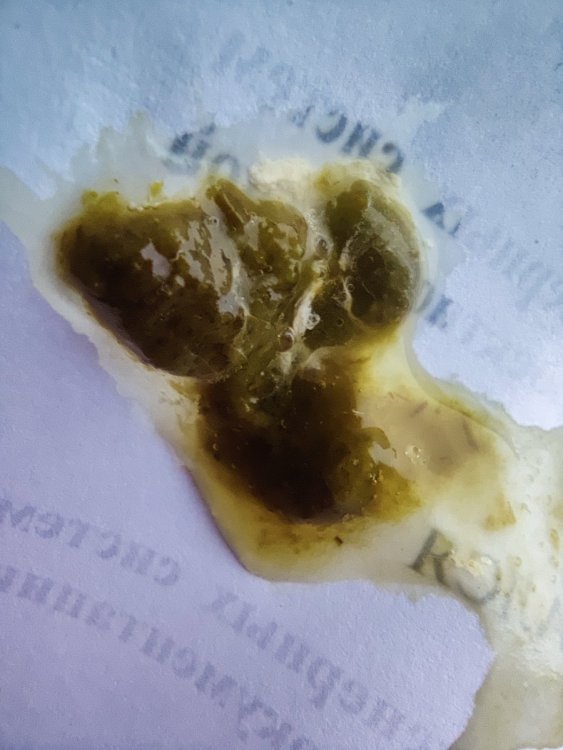

немного размазался но структура сохранена. в основном было такое + вокруг лужицы как на след фото. вот сейчас много такого. сами каки вот такие до этого было чуть более оформленное. сейчас ухудшаться стало. сегодня срыгивали кашу из зоба. вес на данный момент 168 вот на последних фото свежак. в основном такое было. кормлю еще раз распаренной пшеницей. в клюв где-то по 4-8 кубиков за кормление из вот такого устройства кормить стараюсь так чтобы вес поддерживался и чуть сверху еще пару грам

Помет сейчас Вес 238 Истерики продолжаются. Из-за них вертячка вернулась, голова назад прямо закручивается. Успокаивается лишь когда буквально жрёт, как свинья, из миски кашу 😂 Клевать умеет и способен. Но требует, чтоб давали как ребёнку. Голос уже сегодня начал меняться, он взрослеет. Рвоты нет ни разу, все переваривает. Ципрофлоксацин будет 2 недели 1 февраля, затем все можно уже по идее. Флук продолжу. 21 день будет 5 февраля. Но я лучше дам 4 недели, это до 12 февраля Панкреатин закончен уже который день. Нистатин вместе с флуком по срокам -

У нас печальная новость. Утром, когда пришли голубенок был мертвый. Вчера вечером был нормальный, съел почти все зерно, что было у него в коробке. Помета было тоже много, пришлось мыть ему лапы. Помет был не жидкий, темно зеленого цвета. Дали ему все препараты, но он был какой то вялый, не такой, как раньше, Что с ним могло случиться не понятно. Очень жалко его, хороший был голубок, не такой, как все. Раньше тоже были не понятные смерти, вечером все нормально, наутро были мертвы. Но что делать. будем продолжать лечить, есть уже один с простудой и соплями, живет у нас уже несколько месяцев, у него сломано крыло и приболел немного. -

у голубя со вчерашнего дня помет стал насыщенного темно-зеленого цвета, хоть он и ест сам, но почти от всего отказывается кроме льна и семечек, поэтому начали его докармливать кашей домашней (перемолотые: горох, перловка, чечевица) сегодня утром обратила внимание, что сильно пахнет от помета (за ночь). запах кислый, похож на запах творога или кефира. каша за ночь из зоба ушла. к лечению: метронидазол (инфуз) 1.4 х 2р/д; викасол 0.1 х 1р/д и нистатин 1/4 2р/д. Добавила сегодня гепатовет 0.3мл (вечером столько же дам) будет 0.3 х 2р/д фото помета за ночь, который пахнет приложила. подскажите, пожалуйста, кандидоз развивается? нистатин не справляет? или может что-то другое развиваться на фоне приема метронидазола? Восоквицы стали светлее? Чихи по-прежнему есть, но не такие частые. Наросты в горле (в видимой части) остаются, маленькие белые, сфоткать не получается. Самый тревожный сигнал — это помет и то, что голубь ничего не ест. Когда он только прилетел, он хотел есть, просто у него не получалось. Сейчас совсем не ест. Только если положить семечку — ее тут же увидит и съест. Почему так? У него сильная боль в горле? Получается, мы уже неделю на лечении, но наросты полностью не исчезли. Просо он тоже отказывается есть. Продолжать кормить кашей? Если да, то что молоть, учитывая такой помет? Кашу начала давать только вчера -